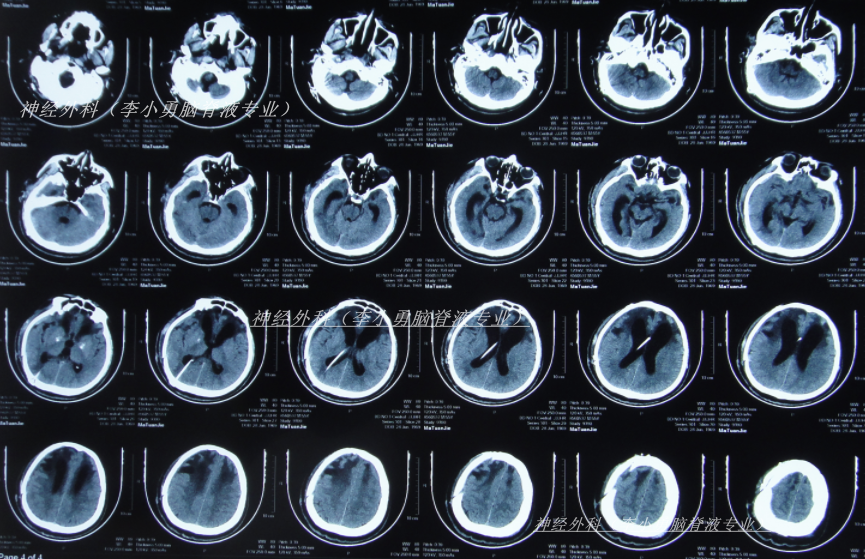

入院当天查头颅CT示颅脑术后改变,脑室扩张,双侧额部硬膜下积液(图-12);胸部CT示两肺炎性病变,心包积液,双侧胸腔积液(图-13)。

图-12:2025年2月4日头颅CT

图-13:2025年2月4日胸部CT

入院当天进行了原脑室腹腔分流管拔除术+脑室外引流术(图-14)。

图-14:2025年2月4日术后头颅CT

住院治疗5天即2025年2月8日,查头颅CT示脑室有缩小(图-15)。

图-15:2025年2月8日头颅CT